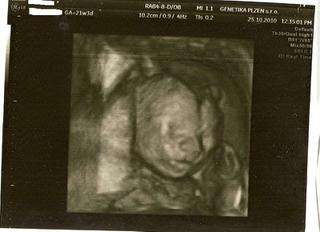

@m.evzenie, o fotečky jsem si vždy říkala. Taky jich mám hromadu 🙂 Třeba z velkého UTZ ve 20tt mám 8 fotek 🙂

Ahoj holky 🙂 , tak včerejší kontroly ok 😵 , genetika ok 😵 (3* hurá, vyhnuli jsme se plodovce ), utz srdíčka taky ok 😵 a na 3d fotce máme vyfocenou pipinku, takže u nás je jasno 😀 . a dr. se s tipem v tom 13.tt týdnu nemýlil 😎 i . Jdu dočíst 😉 .